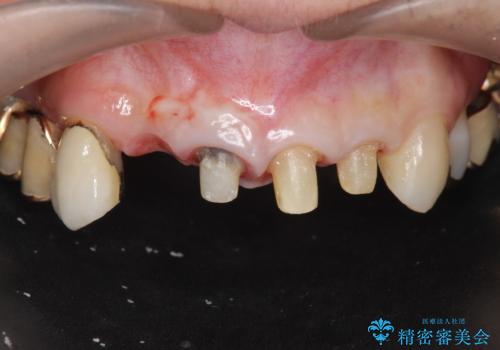

- 前歯の痛み・排膿・ぐらつきの改善を求めて来院されました。

視診・X線写真検査より根尖性歯周炎が認められ再治療が必要な状態です。

再根管治療を行うべくクラウン除去を行ったところ、右上側切歯に保存不可能な垂直性の破折が認められたため抜去が必要になりました。

即切歯の抜歯を行う場合犬歯を含めたブリッジによる補綴計画を立てることが多いですが、今回は犬歯から大臼歯にかかる大きなブリッジが既に装着されていたため予算とご希望を相談し前歯のみの延長ブリッジ補綴で治療を行っていくこととしました。